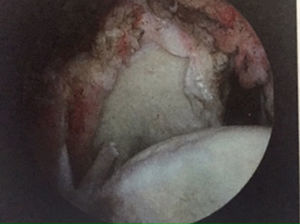

Evidencia de reparación con doble fila o fila sencillaLa reparación artroscópica del manguito de los rotadores es uno de los procedimientos quirúrgicos más comunes y cada vez aparecen nuevas técnicas quirúrgicas, nuevos diseños de anclajes y suturas para tratar de obtener siempre los mejores resultados, los cuales son similares a la técnica abierta, pero con menor morbilidad34,35. Las imágenes radiológicas han mostrado que el porcentaje de rerroturas en técnicas de reparación artroscópica va desde el 30 hasta el 94%, especialmente en el caso de roturas masivas en pacientes mayores36,37.

Una de las limitaciones más importantes que tiene la técnica artroscópica utilizando las suturas con anclaje es poder reproducir la inserción natural del manguito de los rotadores en su huella original13. Por esta razón se han desarrollado técnicas quirúrgicas que tratan de reproducir la inserción natural del manguito de los rotadores con la técnica basada en el concepto de la doble fila38,39. Esta técnica quirúrgica tiene un concepto biomecánico muy claro, que es aumentar la zona de contacto entre el tendón y el hueso en su zona de inserción40,41. Muchos de estos estudios se realizaron en modelos animales o cadáveres sin tener en cuenta cuál era la correlación entre la restauración de la huella del manguito de los rotadores y los resultados clínicos al realizar este tipo de técnica. Existe una muy pobre evidencia en la bibliografía que muestre las ventajas de esta técnica comparándola con la técnica convencional de una sola fila42,43.